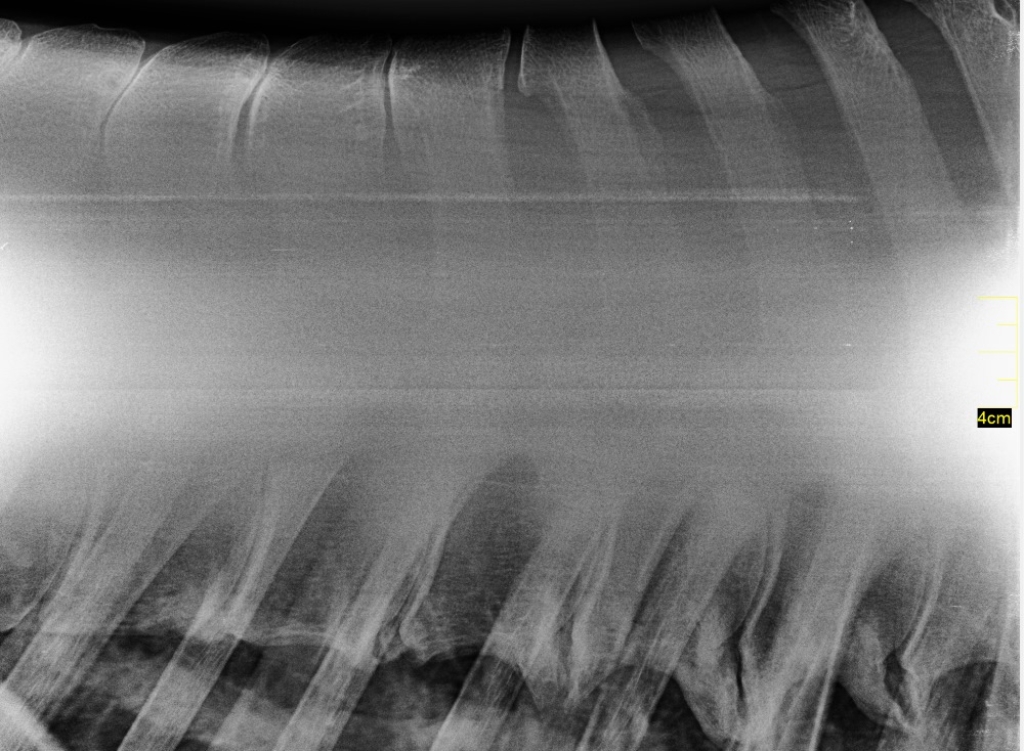

Links: Overgang van de borstwervels naar de lendenen

Rechts: Röntgenfoto van de overgang van borst- naar lendenwervels

Overgang van de borstwervels naar de lendenen

Röntgenfoto van de overgang van borst- naar lendenwervels